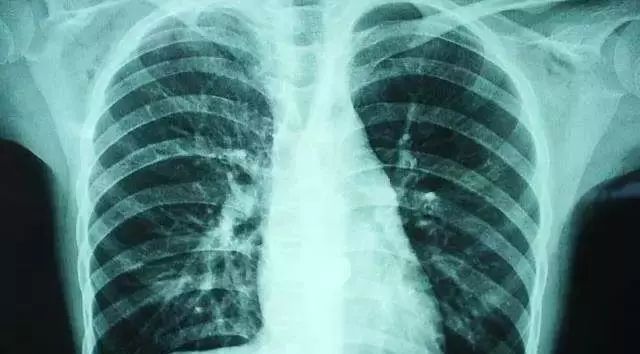

这是一个呼吸道引发肺炎的盆友,连吃大半个月到医院复查的照片↓↓